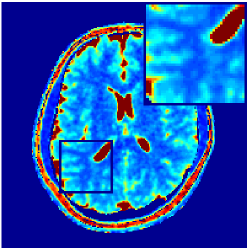

Two sets of experiments were conducted here: first, we used the 2D and 3D acquisition sequences for scanning a healthy volunteer’s brain (real-world acquisitions). Figures 6 and 7 display the parametric maps reconstructed from 2D spiral and radial readouts. We computed the T1, T2 and proton density (PD) maps using baseline reconstruction algorithms ZF, VS, LR, FLOR, AIR-MRF and our proposed LRTV. While baselines use DM either for quantitative inference or also during reconstruction (i.e. AIR-MRF), we further compare the DM-free LRTV’s performance when cascaded to DM, KM and MRFResnet for quantitative inference. For the 3D spiral acquisitions we compared LRTV and its closest competitor VS in Figure 8. Outcomes from other tested algorithm are displayed in the supplementary materials (Figure S5). Since FLOR does not use dimensionality-reduction, our system ran out of memory during 3D reconstruction; hence results are not reported in this case.

VI-E1 Discussion

The LRTV-DM and LRTV-MRFResnet perform on par, and both outperform all tested baselines for reconstructing T1, T2 and PD maps in all acquisition schemes. This can be observed both visually in Figures 6, 7, 8, S2 and S3, and quantitatively in Table IV across all tested metrics. Other baselines were unable to successfully remove the under-sampling artefacts in TSMIs, and these errors propagated to the parameter inference phase and resulted in inaccurate maps. Temporal-only priors incorporated within LR are shown insufficient to regularise the inverse problem and LR sometimes (e.g. 2D spiral acquisitions) can admit solutions with even stronger artefacts than the model-free ZF baseline. This issue was previously studied for other non-Cartesian MRF readouts that similar to our spiral/radial trajectories, miss to sample the corners of the k-space in all timeframes (see section 2.2.2 and figure 2 in [19]). In the absence of reference for the k-space corners information, the LR iterations despite minimising the objective can converge to solutions with high-frequency artefacts, as visible in the computed maps. This highlights the need for adding an appropriate spatial-domain regularisation. FLOR reduces the LR’s artefacts but this improvement is limited because the suggested nuclear norm penalty does not incorporate an explicit spatial regularisation. Further for reducing artefacts, FLOR can introduce an undesirable bias in the computed T1/T2 maps e.g. see error maps in Figures S2 and S3. The non model-based VS baseline incorporates spatial regularisation and results in spatially smoother maps than ZF and LR, but it is unable to output artefact-free images. Further and consistent with our in-vitro experiment, we observe that VS overestimates the T2 values (e.g. in White and Grey matter regions) in tested 2D acquisitions i.e. the spatial regularisation trades off agains the quantification accuracy. The model-based AIR-MRF adds spatial regularisation through 2D/3D low-pass Gaussian filters however this trades off the sharpness of the computed maps and can increase the errors at the tissue boundaries (we searched Gaussian spreads that keep the blurs and high-frequency artefacts minimal). For our acquisition readouts, Gaussian filters performed better than disk filters of [19] for avoiding strong Gibbs artefacts. On the other hand, the spatiotemporally regularised LRTV greatly improves the TSMI reconstructions i.e. 4 dB enhancement compared to the closest competitor baseline (Table IV). This enables computing accurate and aliased-free multi-parametric inference using DM or the DM-free learning-based alternative MRFResnet as visible in Figures 6, 7, 8, S2 and S3. MRResnet and DM score competitive quantitative inference results i.e. T1 and T2 MAPE less than 5% and 9%, respectively (Table IV). KM also outputs comparably accurate T1 maps, however this shallow learning model despite having a model size larger than MRFResnet, is unable to learn accurate T2/PD quantification and it results in poor estimated maps, consistent with our observations in section VI-C.